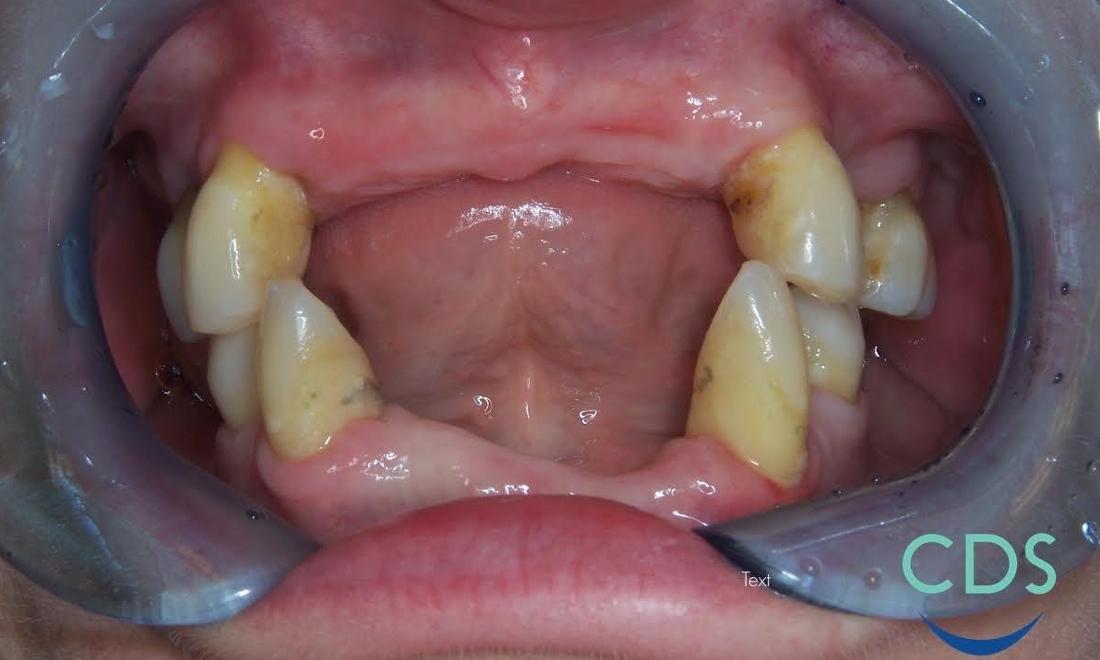

This patient came in will ill-fitting partials and was interested in having the remaining teeth removed to achieve better aesthetics. Because of work, she did not want to go without teeth, so we extracted her remaining teeth and placed her in dentures the same day. Typically, this isn't done to allow for proper healing, but the patient eventually had these relined for a more comfortable fit. We had an excellent outcome in this case and the patient was very happy!